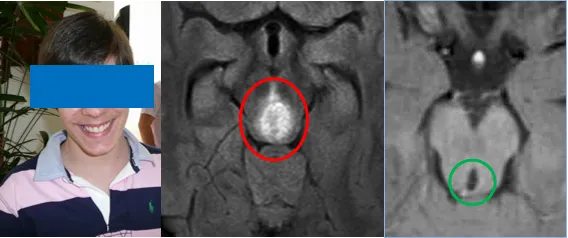

脑干胶质瘤患者生存期究竟有多长?临床预后存在显著差异,从不足1年到5年、10年不等。然而,13岁高级别脑干胶质瘤患者马修术后15年不仅存活,且生活质量优异。

13岁患者马修在校担任班长职务,学习认真负责,性格开朗稳定,与同学保持良好关系。学期中途,他突然决定申请长期休假。亲密朋友纷纷关心其状况,但马修异常保持沉默。

经巴教授15年长期随访,马修现已顺利进入成年期。尽管童年时期遭遇重大疾病,但成功的手术治疗为他赢得了完整的少年和青年时期。见证目前笑容满面、精神饱满的马修,父母无比庆幸当年的治疗选择不仅未造成严重后遗症,反而挽救了他的生命。

手术几天后按计划进行,巴教授团队经过数小时精心操作成功切除肿瘤。术后病理检查显示为WHO Ⅲ级间变性星形细胞瘤(Anaplastic Astrocytoma)。通过巴教授15年长期随访,马修现已顺利进入成年阶段。尽管童年时期遭遇重大疾病,但成功的手术治疗为他争取了完整的少年和青年时期。目睹目前笑容满面、精神饱满的马修,父母深感庆幸当年的治疗选择不仅避免严重后遗症,更挽救了他的生命。术后影像学检查结果显示良好。